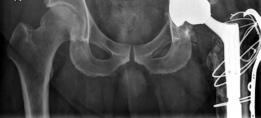

(Figs. 19.17, 19.18, and 19.19)

Diagnosis : Left total hip arthroplasty wear and aseptic loosening (Figs. 19.17, 19.18 and 19.19)

3. Acetabulum—once the acetabular components were removed, the bony void was classified as a Paprosky type IIIB defect, and we found that an appropriately sized trabecular metal augment could be used to buttress the roof of the acetabulum. Also, a porous tantalum multi-hole shell with impaction bone grafting was selected to achieve stability of the acetabular component.